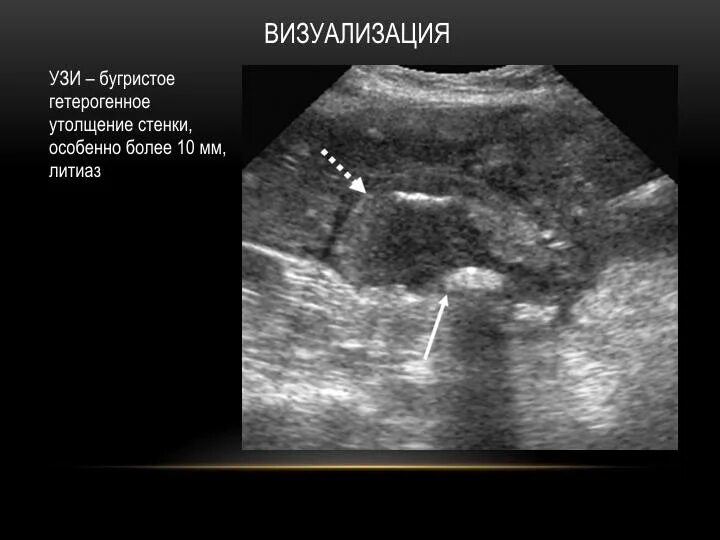

Сердце визуализация затруднена